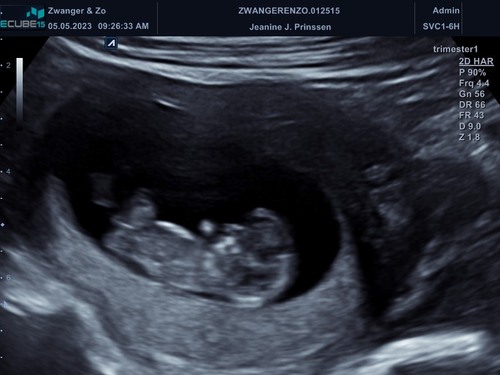

Iemand een idee? Denk wat vroeg, maar je weet t nooit 😋 11+2